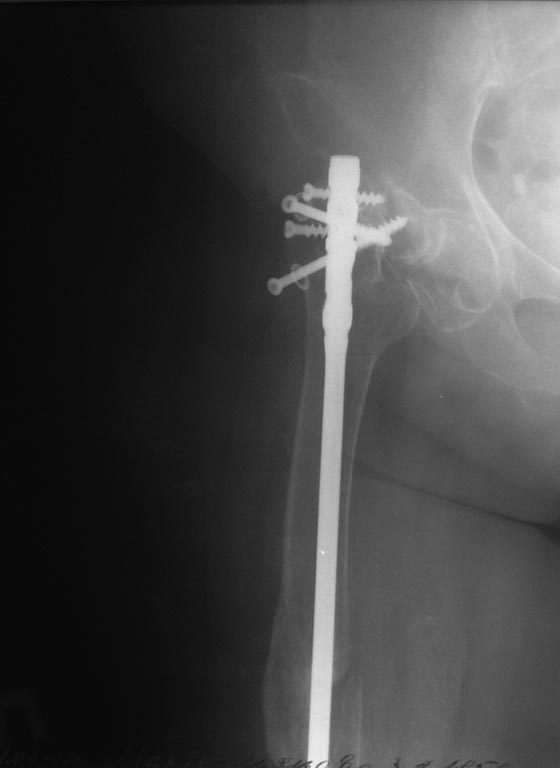

нужна помощь в дальнейшей тактике по пациентке 62 года вес около 90 кг

. передвигается  при помощи костылей . 2011 году остеосинтез правого

бедра на данный момент ложный сустав шейки правого бедра. что бы

отправить на ВМП нужно удалить металл, боимся за диафиз бедра.  как

поступить и кто сможет помочь?